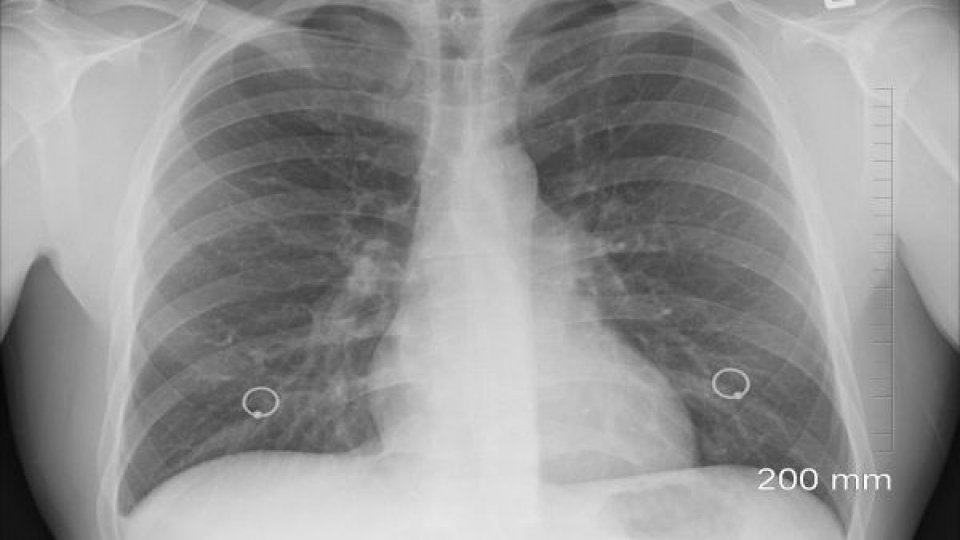

Metodele de screening pentru depistarea activă a tuberculozei includ radiografia pulmonară, testul tuberculinic (Mantoux), testul IGRA (Interferon Gamma Release Assay) și examinarea sputei pentru detectarea bacteriilor de la nivelul plămânilor.

Caravana medicală mobilă este dotată cu aparatură de radiologie mobilă de ultimă generaţie şi beneficiază de cea mai avansată metodă de identificare a infecţiei cu bacilul tuberculozei, diagnostic molecular rapid, teste GeneXpert.

De asemenea, dispune de un program de inteligenţă artificială care ajută la depistarea tuberculozei şi a altor 14 patologii pulmonare, iar serviciile medicale din caravană sunt asigurate de personal medical de specialitate.